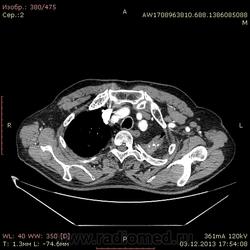

Доброго времени суток уважаемые форумчани! :)Провели исследование КТ грудной клетки с контрастированием, для выявления аневризмы грудного отдела аорты. В результате увидели это:

Ребята, вы что, какая жидкость? Чистая известь, посмотрите в костном окне. Отставить натив (в данном случае, хотя для аневризм он обычно нужен). Отставить тромбоз верхней полой вены (потоковые артефакты, не дело вены в артериальную фазу оценивать). Отставить аневризму  аорты, поперчник восходящего отдела на уровне легочного ствола 42мм. А вот легочная гипертензия, здравствуй: поперечник легочного ствола - 37мм, ПЛА - 25мм, ЛЛА - 25мм, НАо - 25-34мм.

намерил аорту, всё таки есть аневризматическое расширение луковицы